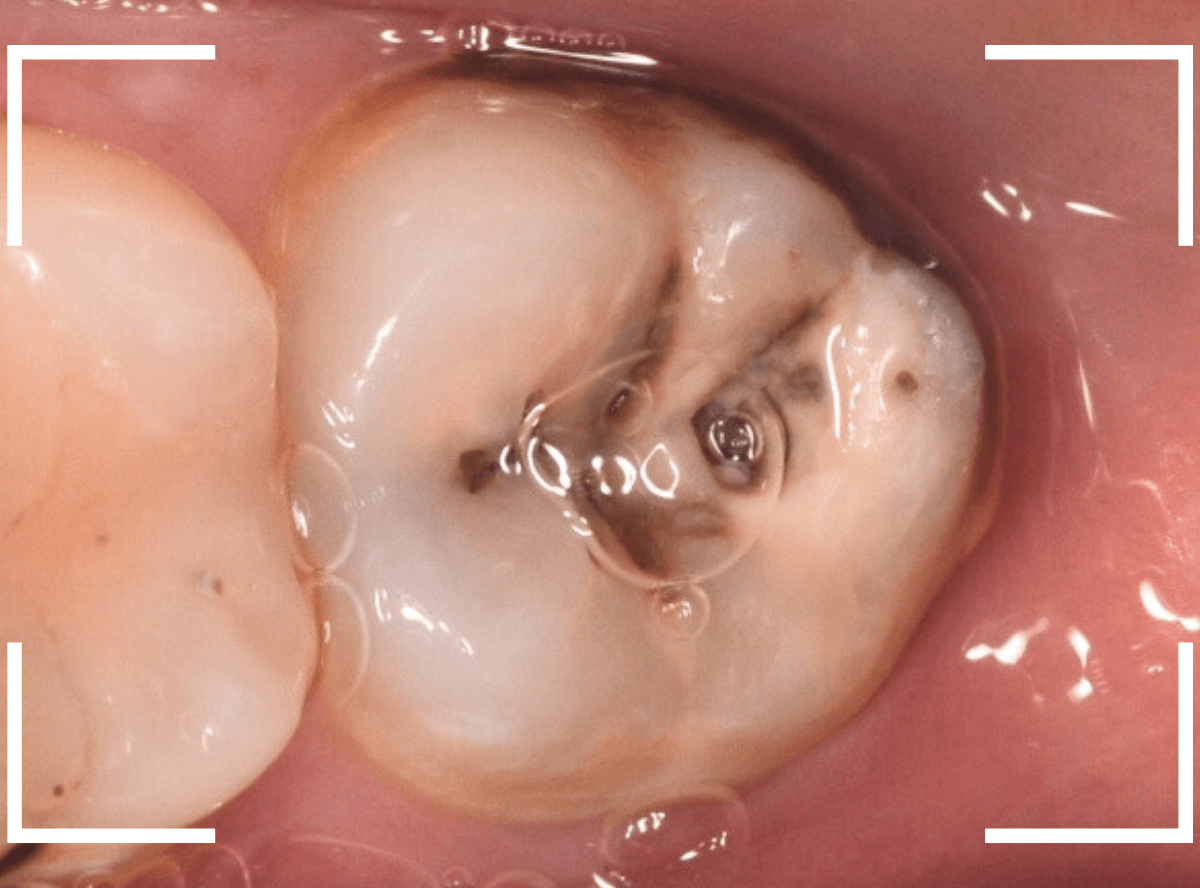

ここでは、比較的簡単なおやしらずの抜歯の例を中心にご紹介します。

このようなおやしらず、あなたはありませんか?